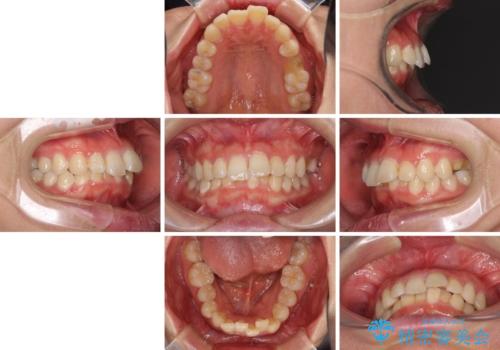

インビザラインが続けられない ワイヤー矯正に切り替えてデコボコを改善

- 1年7ヶ月

- 10-30回

- デコボコの歯列が気になるとことで来院された患者様です。

歯列不正としては軽度であったため、インビザラインでもワイヤー装置でも対応可能でしたが、ご本人の希望によりインビザラインによる矯正治療を行うこととしました。

マウスピース矯正は、自己管理が非常に重要と事前にお伝えしておりましたが、毎日のマウスピース装着が遵守できず、ワイヤー装置での矯正治療へ変更することとなりました。

インビザラインからワイヤー装置へ変更すると、費用が追加となるため、ワイヤー装置は目立つものの費用を抑えることのできるメタルブラケットを使用しました。